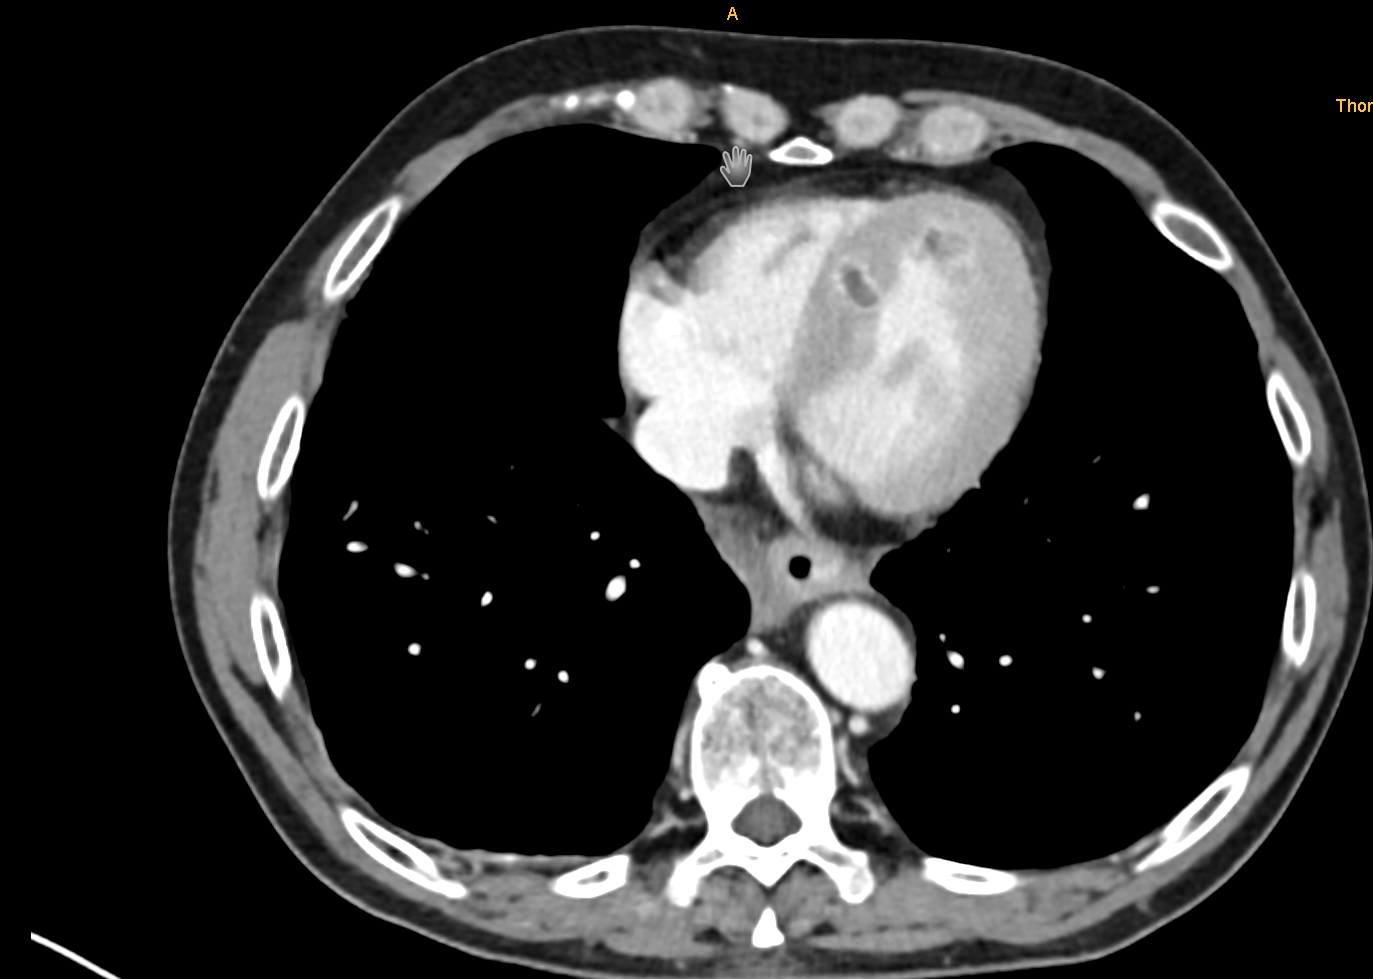

Bei einem 57-jährigen Patienten mit metastasiertem klarzelligem RCC zeigten sich in der CT-Verlaufskontrolle zwei neue, kontrastmittelanreichernde Läsionen im Myokard anteroapikal und septal, die differenzialdiagnostisch nicht sicher zwischen Thromben und Metastasen zu unterscheiden waren. Der Patient berichtete über Palpitationen, jedoch keine Dyspnoe oder Thoraxschmerzen. Das EKG ergab T-Wellen-Negativierungen in den Ableitungen V1–V6, NT-proBNP war mit 1670 pg/ml erhöht. Die transthorakale Echokardiographie zeigte eine fokale Wandverdickung anteroapikal und inferoseptal bei scharfer Abgrenzung des Endokards. Die linksventrikuläre Ejektionsfraktion lag bei etwa 55 %, Auffälligkeiten des rechten Ventrikels bestanden nicht. Zur differenzialdiagnostischen Abgrenzung erfolgte eine Kontrastechokardiographie, in der beide Läsionen eine deutliche Hypervaskularisation zeigten. Dieser Befund legte eine metastatische Genese nahe und war nicht mit dem avaskulären Erscheinungsbild thrombotischer Strukturen vereinbar. Aufgrund der Tumorprogression erfolgte ein Wechsel der systemischen Therapie von Sunitinib auf Belzutifan. Unter fortlaufender kardioonkologischer Betreuung ist der Patient derzeit klinisch stabil.